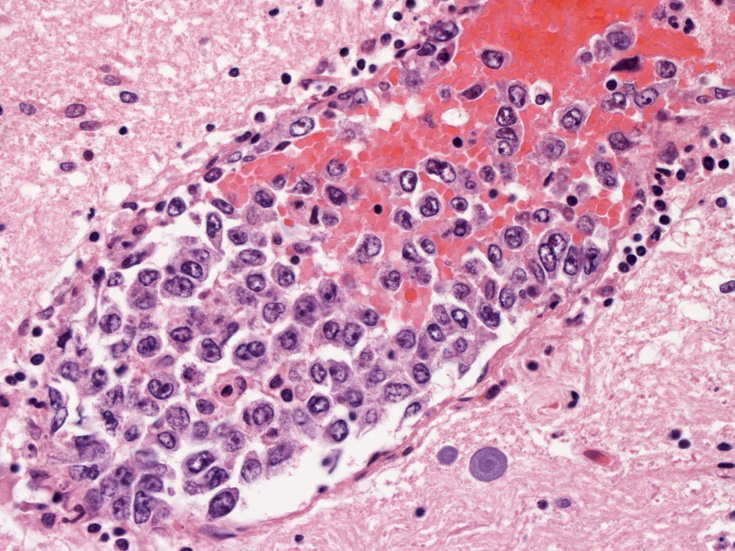

肺B;小気管支動脈, 肺動脈内を腫瘍細胞が閉塞する. 動脈内膜に浸潤性増殖している(B)。